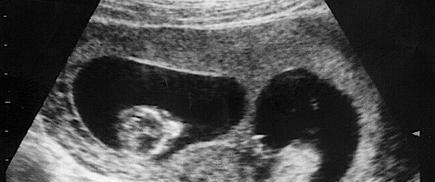

怀胎十月一朝分娩,在很多人的印象中只要到了产房,孩子很快就能出生,不过这也仅限于正常的一个胎儿,但要是两个及以上的胎儿,有可能就会出现分两天出生的情况。

胡女士是一位38岁的高龄孕妈,非常幸运的是,虽然是高龄孕妇,但是怀的却是龙凤胎,这可让全家高兴坏了,一次怀俩,儿女双全这是多少人梦寐以求的事情了。

由于是两个孩子,到了孕晚期的时候全家都做好了要早产的准备,果不其然胎儿在30周的时候就开始发动了,丈夫赶紧带妻子去医院,经过诊断后,胡女士确实是要生了。

医生连忙准备手术,在经历几个小时的分娩,胡女士生下了一个女儿,就在陈女士想要一鼓作气把儿子也生出来的时候,被医生告知子宫硬已经停止收缩,如果继续可能会有危险,需要延期分娩。

胡女士不懂这些专业用语,只能听从医生的,就这样陈女士出了产房,3天后又进入了产房,成功生下儿子,胡女士觉得这次经历非常有意义,就在社交软件上记录了下来,没想到却意外地火了。

一般情况下多胞胎出生的时间间隔都不会相差太多,大约都是在10分钟以内,而像这种子宫停止收缩,分两天分娩的情况也是存在的,在生活中也并不是特别奇怪的事情。

每个胎儿都有自己的一个房间,两个孩子就有两间房,并且之间互不打扰,因此才会出现一个孩子出生之后,产妇宫口关闭的情况,在这种情况下为了胎儿的安全着想,一般医生都会停止手术,继续待产。